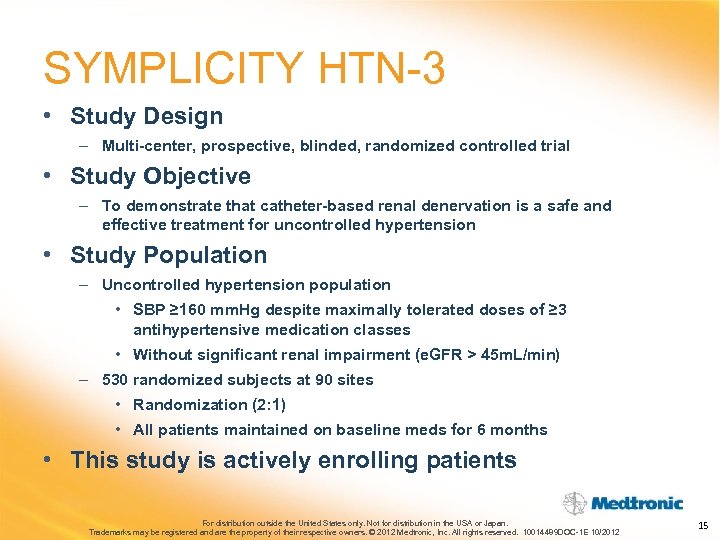

SYMPLICITY HTN-3 • Study Design – Multi-center, prospective, blinded, randomized controlled trial • Study Objective – To demonstrate that catheter-based renal denervation is a safe and effective treatment for uncontrolled hypertension • Study Population – Uncontrolled hypertension population • SBP ≥ 160 mm. Hg despite maximally tolerated doses of ≥ 3 antihypertensive medication classes • Without significant renal impairment (e. GFR > 45 m. L/min) – 530 randomized subjects at 90 sites • Randomization (2: 1) • All patients maintained on baseline meds for 6 months • This study is actively enrolling patients For distribution outside the United States only. Not for distribution in the USA or Japan. Trademarks may be registered and are the property of their respective owners. © 2012 Medtronic, Inc. All rights reserved. 10014489 DOC-1 E 10/2012 15

SYMPLICITY HTN-3 • Study Design – Multi-center, prospective, blinded, randomized controlled trial • Study Objective – To demonstrate that catheter-based renal denervation is a safe and effective treatment for uncontrolled hypertension • Study Population – Uncontrolled hypertension population • SBP ≥ 160 mm. Hg despite maximally tolerated doses of ≥ 3 antihypertensive medication classes • Without significant renal impairment (e. GFR > 45 m. L/min) – 530 randomized subjects at 90 sites • Randomization (2: 1) • All patients maintained on baseline meds for 6 months • This study is actively enrolling patients For distribution outside the United States only. Not for distribution in the USA or Japan. Trademarks may be registered and are the property of their respective owners. © 2012 Medtronic, Inc. All rights reserved. 10014489 DOC-1 E 10/2012 15